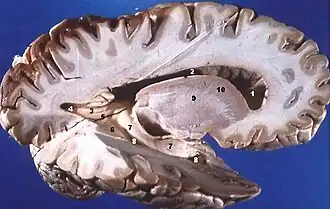

Dissekterede menneskelig hjerne, lateralt vue, der viser grå substans (de mørkere dele), og hvid substans (den indre og prominenter hvidere dele).